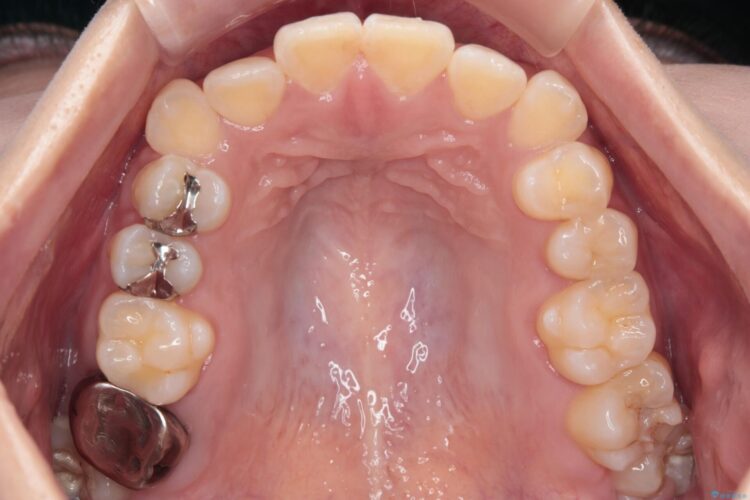

八重歯とガタつきが気になるとご来院された患者様です。

精密検査の結果、抜歯はせずIPR(歯と歯の間を削る処置)を行い、目立ちにくい審美ワイヤー装置にて歯列拡大を行うことで歯列を整える治療計画を立てました。